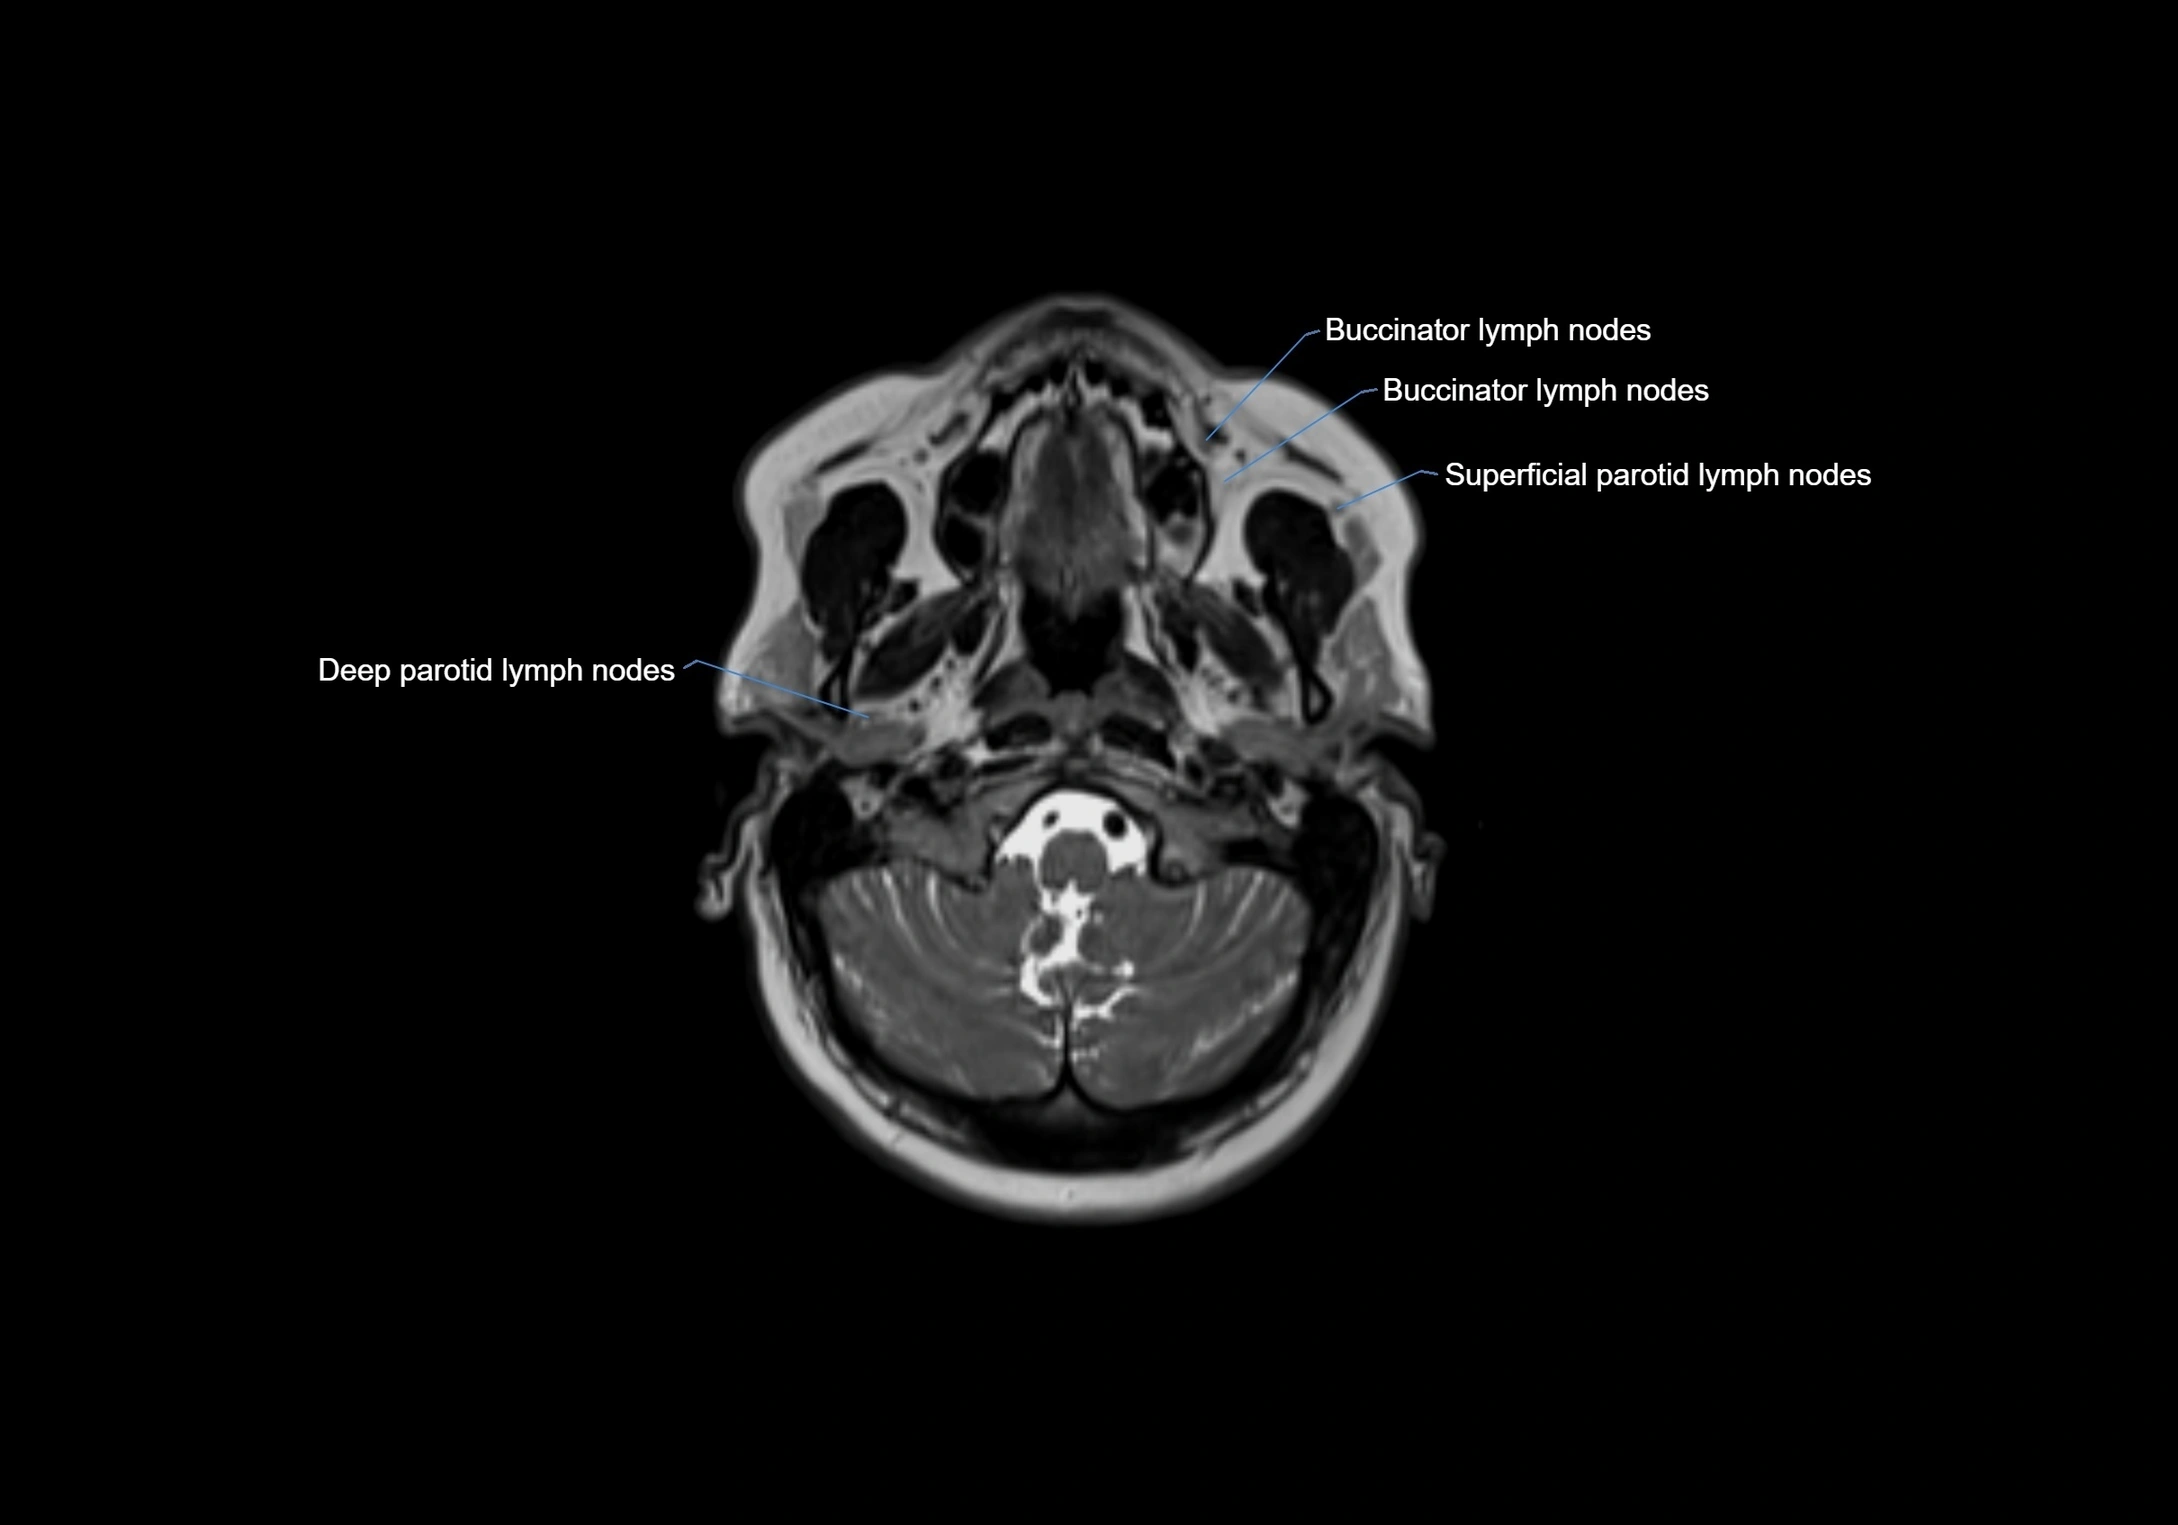

Location

• Found along primary lymph node chains, including preauricular, submandibular, parotid, and occipital regions

• Embedded in subcutaneous fat or superficial fascia, often lateral or posterior to primary nodes

MRI Appearance

T1-weighted images:

• Normal accessory nodes appear as small, oval hypointense to intermediate signal structures within subcutaneous fat

• Surrounded by hyperintense fat, enhancing contrast for visualization

• Pathological nodes may appear enlarged or rounded, sometimes with cortical thickening

T2-weighted images:

• Nodes show intermediate signal, with surrounding fat bright

• Useful for detecting edema, inflammation, or infiltration

• Fatty hilum may appear slightly hyperintense relative to cortex

MRI images

image